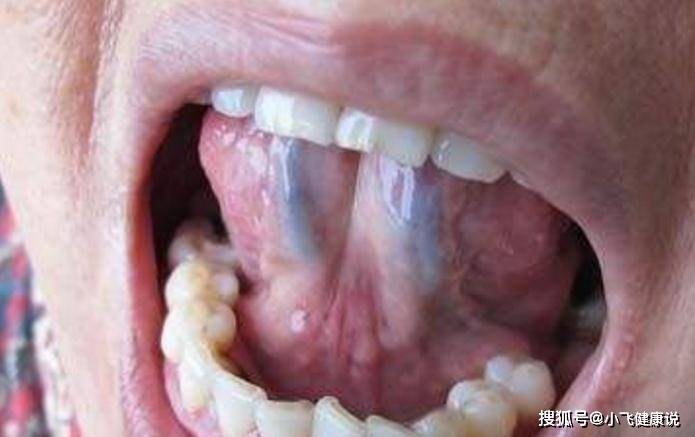

中醫治病追尋「望、聞、問、切」,其中的每一個環節都能夠看出我們身體的內在症狀,今天小編給各位朋友們來介紹的是觀察舌頭看我們身體是否存在隱疾。由於舌頭下面有青筋存在,這些青筋也就是我們的靜脈血管,一旦身體有一些不適症狀出現時,舌底下的青筋會有一些預兆,所以各位朋友們在平時照鏡子的時候可以細心觀察一下。下面不妨隨小編一起來了解一下,當青筋發生哪些變化時預示著身體有症狀存在呢。

1、青筋凸起—血壓高

正常情況下,當我們身體沒有其他不適症狀出現時,舌底的靜脈血管是比較平緩的,沒有突出情況。一旦這些青筋凸起,這可能是由於體內的靜脈存在問題,尤其是當血壓升高時,會出現青筋凸起的狀況。其次,一旦有冠狀動脈受到阻塞,青筋也會呈現突起狀態。

2、青筋發紫—濕氣重

尤其是對於大多數女性朋友來說,體內濕氣過重時,不僅會出現長斑長痘的情況,而且還會影響月經的正常到來。其次,在平時可以觀察舌底下的靜脈血管,一旦出現發紫的現象時,也可能是體內濕氣過重導致的,並且還可能伴隨有大便稀薄,頭暈眼花等症狀,所以一經發現不妨及時調理身體。

3、青筋發紅—熱氣大

根據我們血液的變化,靜脈血管的顏色正常情況下是發青的,所以我們才將它稱為青筋。若是靜脈血管的顏色呈現發紅的狀態時,可能是由於體內熱氣過重導致的,而且還會出現面色發紅,出虛汗等不適症狀。此外,一旦出現這種情況時,一定要及時給我們的身體補充足夠的水分,而且做到飲食清淡,一些辛辣刺激的食物還是不要吃得好。